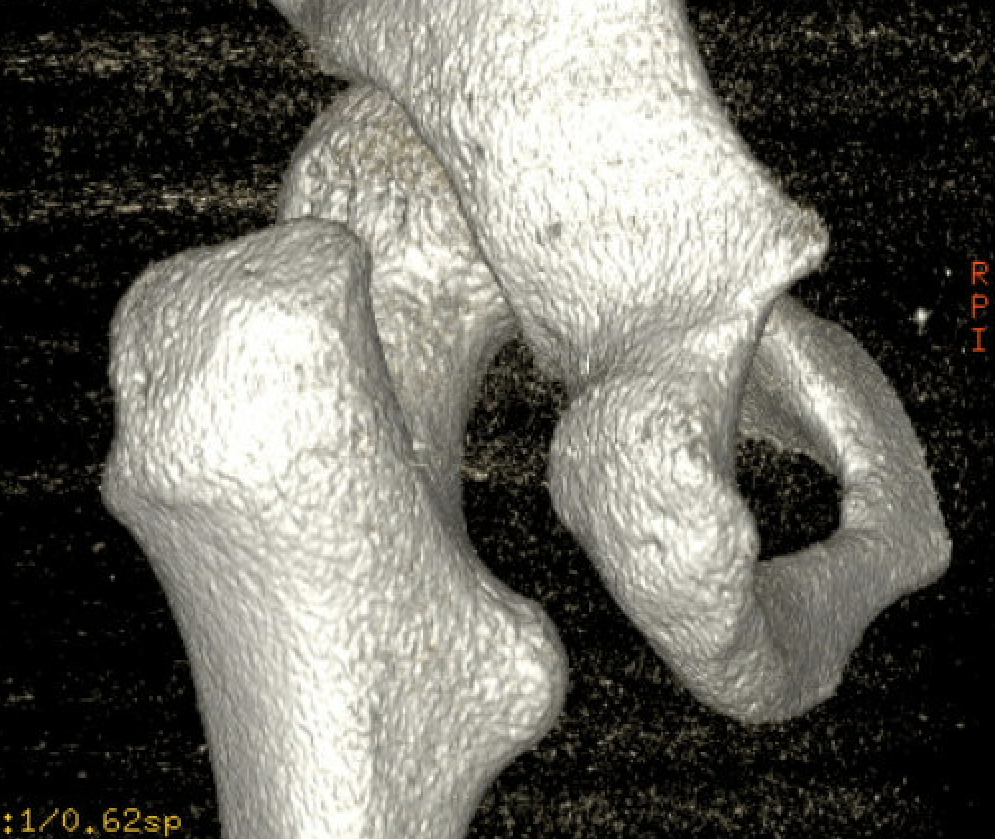

Narrowing of the ischiofemoral space between lateral ischium and lesser trochanter

Entrapment / compression of quadratus femoris

Reduced ischiofemoral space - distance between the lesser trochanter and the ischial tuberosity

Reduced quadratus femoris space - distance between hamstring tendon and iliopsoas

CT